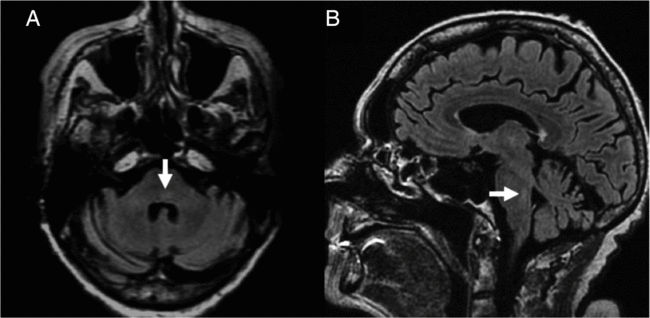

Figure 2: Brain MRI in neuroinvasive WNV infection. On axial (A) and sagittal (B) fluid-attenuated inversion recovery imaging, T2 hyperintensity of the dorsal pons is seen (arrows).

An 81-year-old woman presented with facial weakness preceded by a 2-week flu-like illness. Her past medical history included type 1 diabetes and Crohn’s disease. Neurologic examination revealed facial diplegia in a lower motor neuron distribution, with no other cranial nerve, motor, sensory or coordination deficit (Figure 1). General examination did not demonstrate any cardiorespiratory, gastrointestinal or rheumatological findings. No rash was detected. Brain magnetic resonance imaging (MRI) revealed subtle signal abnormality in the dorsal pons without restricted diffusion (Figure 2). There were findings compatible with a bilateral facial motor axonal neuropathy on nerve conduction studies (NCS); both blink reflexes were absent when bilateral supraorbital nerves were stimulated and recorded over the orbicularis oculi, and bilateral facial motor responses from the nasalis were low in amplitude. Cerebrospinal fluid (CSF) profile demonstrated a neutrophilic-predominant pleocytosis with 120 nucleated cells. Gram stain and culture as well as viral polymerase chain reaction tests for enterovirus, herpes simplex virus and varicella zoster virus were negative in CSF. Serum infectious workup was negative for human immunodeficiency virus, syphilis, hepatitis B, C and Lyme disease. Serum angiotensin-converting enzyme was within normal limits and chest X-ray showed no evidence of sarcoidosis. West Nile virus (WNV) IgM was reactive in both CSF and serum, compatible with acute WNV infection. Unfortunately, she had a complicated course in hospital. Her oral intake was significantly impaired from her facial diplegia and she developed hospital-acquired delirium. Speech language pathologist assessment identified oral stage dysphagia with anterior leakage related to her bilateral facial diplegia as well as an up and down mashing mastication pattern difficulty with bolus transport and lingual thrusting. A gastrojejunostomy tube was placed, but she later developed an upper respiratory tract infection and worsening delirium. Ultimately, she was palliated and the primary goal was comfort-focused care.